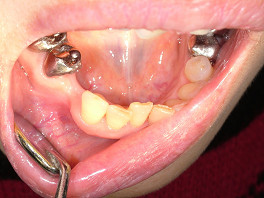

次の方は、歯を全く削らずにきれいにしてほしいということで、大阪から来られた患者さんの左上の前の歯4本を、グラディアで白くしてみました。

歯を全く削らず、表面をナノシールで処理して、グラディアで30分くらいの施術でした。

術前 ↓

術後

右側のすでに被せてある茶色く変色している歯は、大阪の家の近くの歯医者さんで、今回白くなった色に合わせて、被せなおしてもらうとのことです。